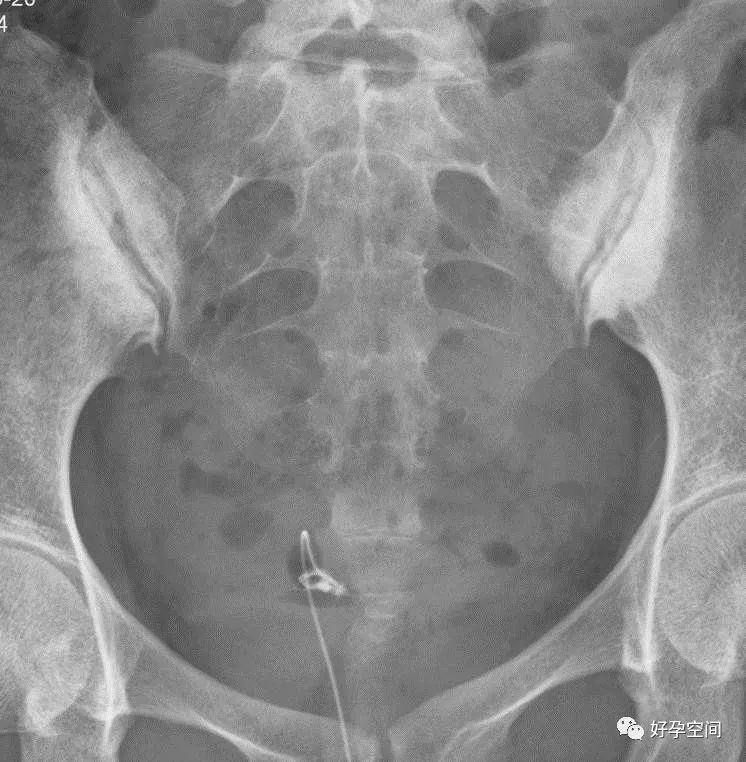

6、子宫肌瘤钙化

盆腔内见类圆形蛋壳样高密度影